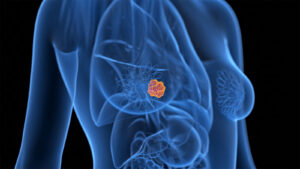

MedPage Today) — A novel strategy for switching breast cancer therapy intrigued members of...